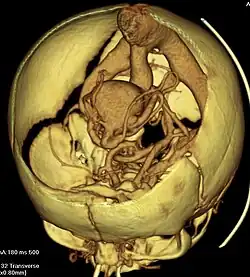

| Axial image from computerized tomography angiogram showing arteriovenous communication in vein of Galen malformation | |